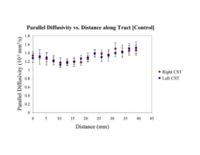

Clustered fibers in the region of the corticospinal tract have been used to identify regions of interest for slice-by-slice measurements of its diffusion properties in normals and tumor subjects. A pilot study (with Monica Lemmond at Harvard Medical School and Stephen Whalen and Alexandra Golby at Brigham and Women's Hospital/HMS) has demonstrated changes in tumor-affected tracts (relative to the contralateral side) beyond the apparent tumor border. A larger study is currently underway.

Monica E. Lemmond, Lauren J. O'Donnell, Stephen Whalen, and Alexandra J. Golby Characterizing Diffusion Along White Matter Tracts Affected by Primary Brain Tumors Abstract accepted to HBM 2007